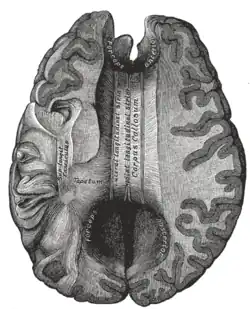

The corpus callosum (Latin for "tough body"), also callosal commissure, is a wide, thick nerve tract, consisting of a flat bundle of commissural fibers, beneath the cerebral cortex in the brain. The corpus callosum is only found in placental mammals.[1] It spans part of the longitudinal fissure, connecting the left and right cerebral hemispheres, enabling communication between them. It is the largest white matter structure in the human brain, about 10 in (250 mm) in length and consisting of 200–300 million axonal projections.[2][3]

On either side of the corpus callosum, the fibers radiate in the white matter and pass to the various parts of the cerebral cortex; those curving forward from the genu into the frontal lobes constitute the forceps minor (also forceps anterior) and those curving backward from the splenium into the occipital lobes, the forceps major (also forceps posterior).[4] Between these two parts is the main body of the fibers, which constitute the tapetum and extend laterally on either side into the temporal lobe, and cover in the central part of the lateral ventricle. The tapetum and anterior commissure share the function of connecting left and right temporal lobes.